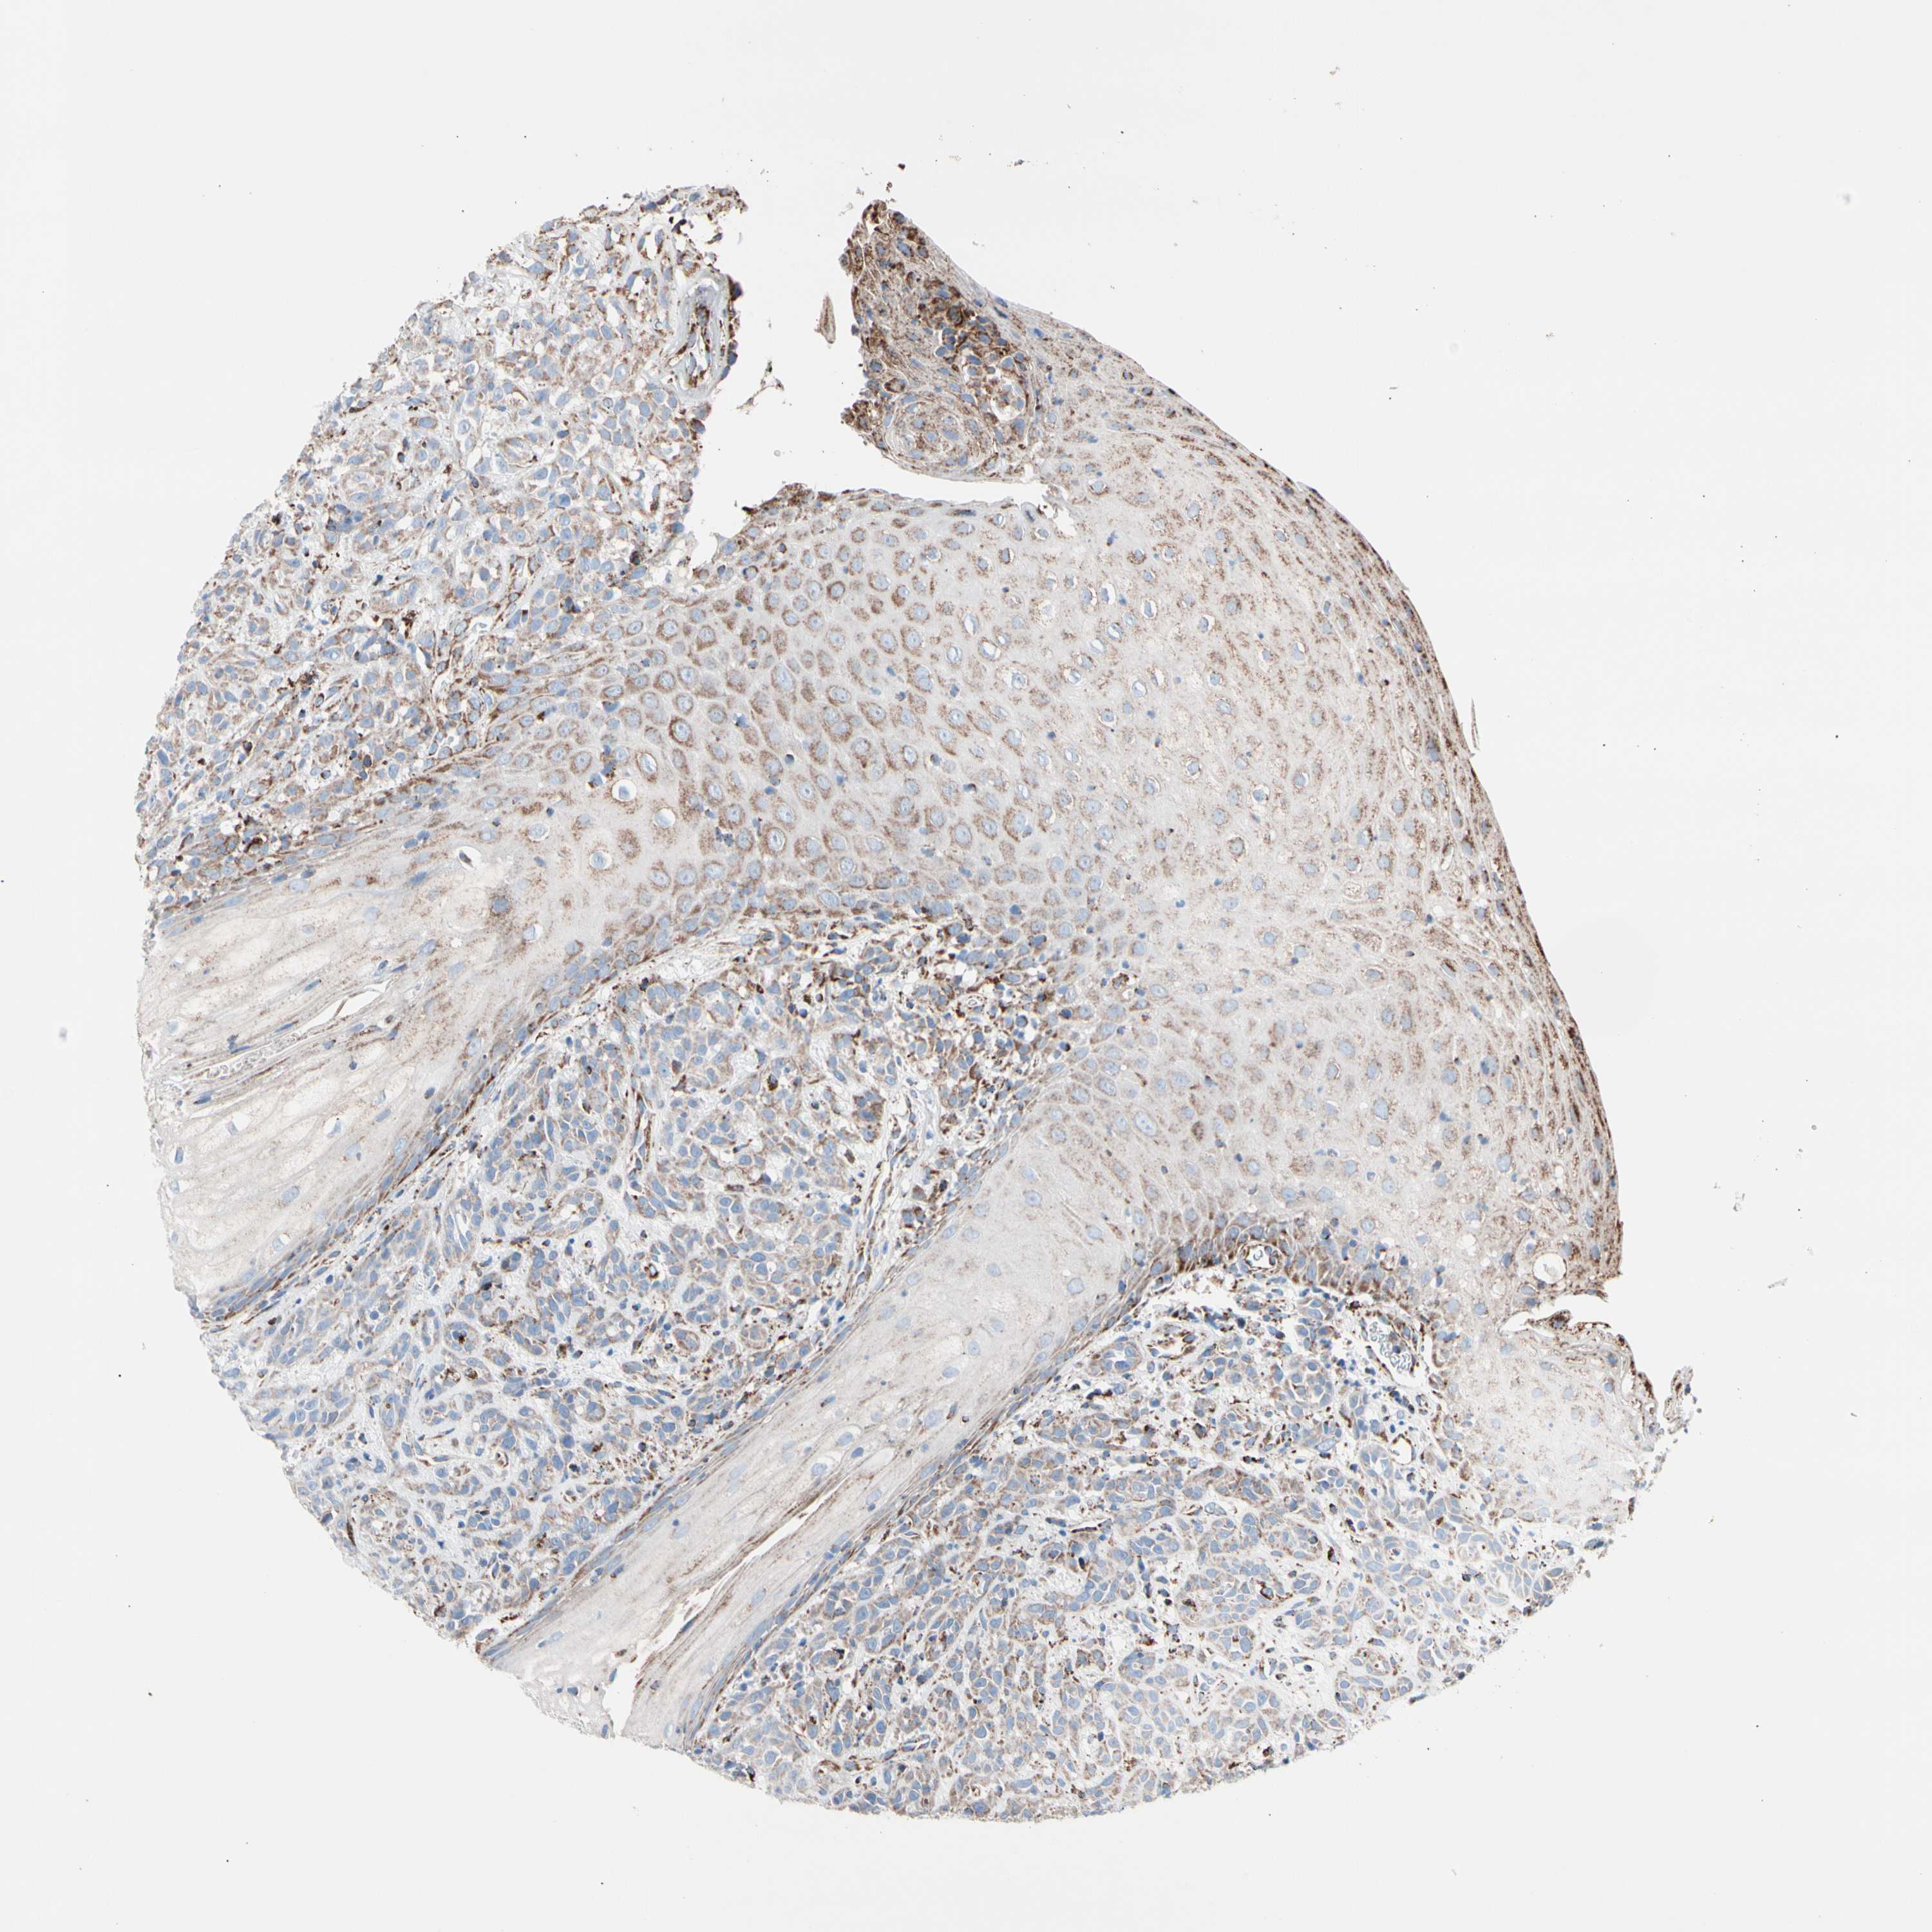

HEAD AND NECK CANCER - Protein expressioni

A mouse-over function shows sample information and annotation data. Click on an image to view it in a full screen mode. Samples can be filtered based on level of antibody staining by selecting one or several of the following categories: high, medium, low and not detected. The assay and annotation is described here.

Antibody stainingi

Antibody staining in the annotated cell types in the current human tissue is reported as not detected, low, medium, or high, based on conventional immunohistochemistry profiling in selected tissues. This score is based on the combination of the staining intensity and fraction of stained cells.

Each image is clickable and will lead to virtual microscopy that enables deeper exploration of all samples and also displays staining intensity scores, fraction scores and subcellular localization as well as patient and tissue information for each sample.

Antibody HPA007043

Antibody HPA007044

Antibody CAB010052

Staining

High

Medium

Low

Not detected

Squamous cell carcinoma, NOS

Adenocarcinoma, NOS

Adenoma, NOS

Squamous cell carcinoma, metastatic, NOS